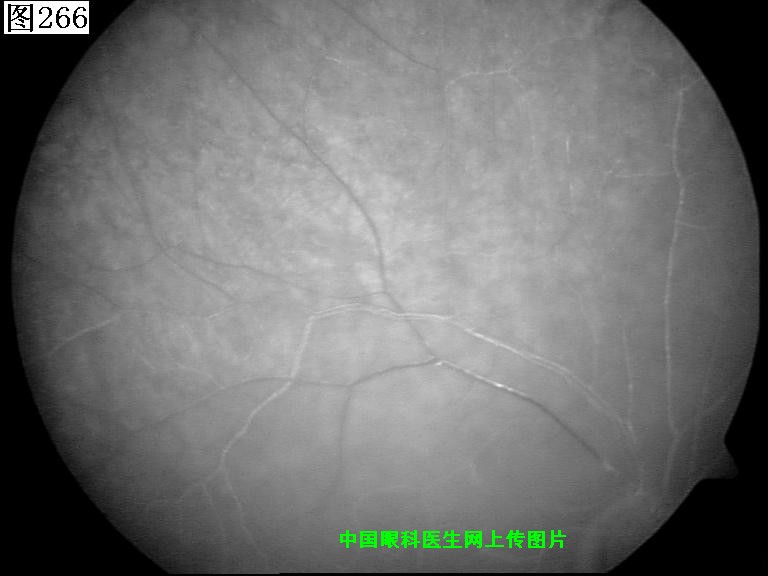

265 266 267 268